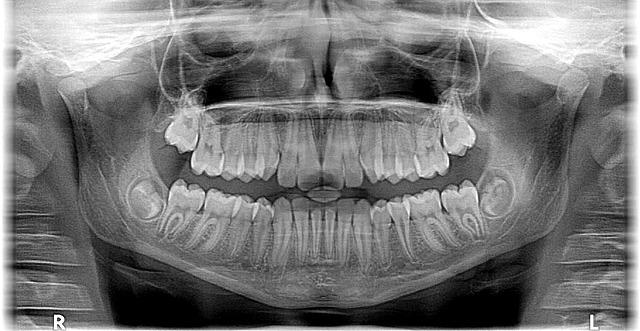

The doctor’s innovative practice is evident in his state-of-the-art facility located at 1632 N. 10th Street, McAllen, TX 78501. Here, advanced technology meets compassionate dentistry. Using cutting-edge tools and methods, Dr. Cazares provides efficient, effective treatments, from traditional braces to innovative clear aligner systems. His expertise allows him to address a wide range of dental issues, ensuring beautiful, healthy smiles for patients of all ages.